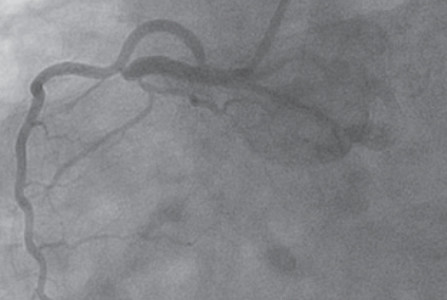

In the hands of experienced operators and high-volume transradial catheterization centers, transradial coronary angiography and intervention offer improved patient comfort, decreased access-site complications, and lower costs without compromising procedural success or long-term outcomes.